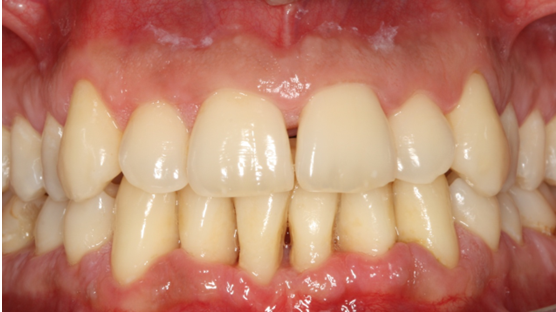

15. Θεραπεία χρόνιας περιοδοντίτιδας σε καπνιστή

Ο ασθενής ηλικίας 50 ετών παρουσίαζε περιοδοντική νόσο προχωρημένης βαρύτητας και ήταν βαρύς καπνιστής. Ανέφερε πόνο στα ούλα, αιμορραγία και έντονη κακοσμία. Παράλληλα με την περιοδοντική θεραπεία, δόθηκε έμφαση στη μείωση του καπνίσματος. Στην κλινική εικόνα κατά την επανεξέταση παρατηρείται απουσία φλεγμονής.

ΑΡΧΙΚΗ ΚΛΙΝΙΚΗ ΕΙΚΟΝΑ

ΤΕΛΙΚΗ ΚΑΤΑΣΤΑΣΗ